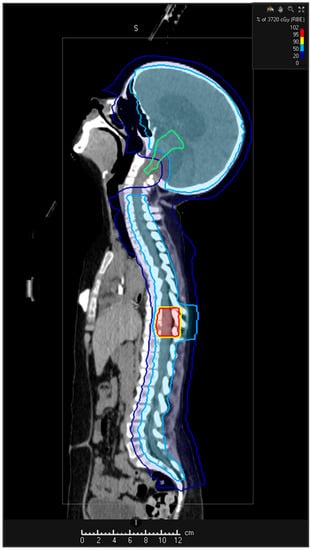

5.2. Re-Irradiation

5.2.1. Re-Irradiation Doses and Volume

5.2.2. Techniques

5.2.5. Proton Beam Therapy